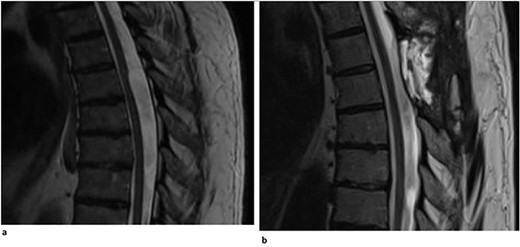

A 62-year-old woman presented with an extensive, multi-decade history of lower back pain that has progressively gotten worse over the last year. She initially presented in clinic with lumbar pain that radiated down her left anterior thigh, as well as significant thoracic pain that worsened with activities. She has a past surgical history of three lumbar laminectomies in 1983, 1988, and 1995 that caused temporary relief of her lumbar radiculopathy. In clinic, she stated that, during long periods of standing, she will experience buttock and lower extremity pain, as well as pain radiating to her anterior thigh and groin. She also said that she had increased difficulty with balance, causing her to use a rolling walker for ambulation. Physical examination demonstrated myelopathic symptoms with 3+ reflexes in both lower extremities and positive Babinski sign bilaterally. MR imaging of the spine was ordered and showed an arachnoid web displacing the spinal cord at the level of T3 (Fig. 3). Her current symptoms were treated nonoperatively with an epidural steroid injection that caused 80% relief of symptoms for 2–3 weeks. Three months later, she returned with increased bilateral shooting pain in the interscapular blade region. The patient will return in 6 months to proceed with a repeat thoracic MRI to evaluate for any interval changes.

Dorsal indentation demonstrated in thoracic spine preoperatively (Patient C).